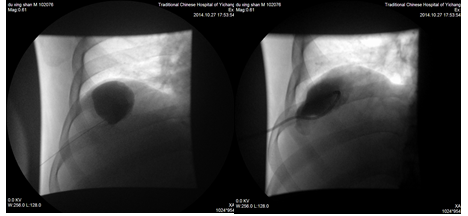

肝、肾囊肿是常见疾病,药物治疗基本无效,外科手术创伤大,费用高,并发症高,在影像学引导下穿刺引流及硬化治疗现在已为首选治疗。

典型病例、患者、男、55岁,因发现巨大肝囊肿,在我院介入科行CT引导下穿刺引流+硬化治疗术后恢复良好。